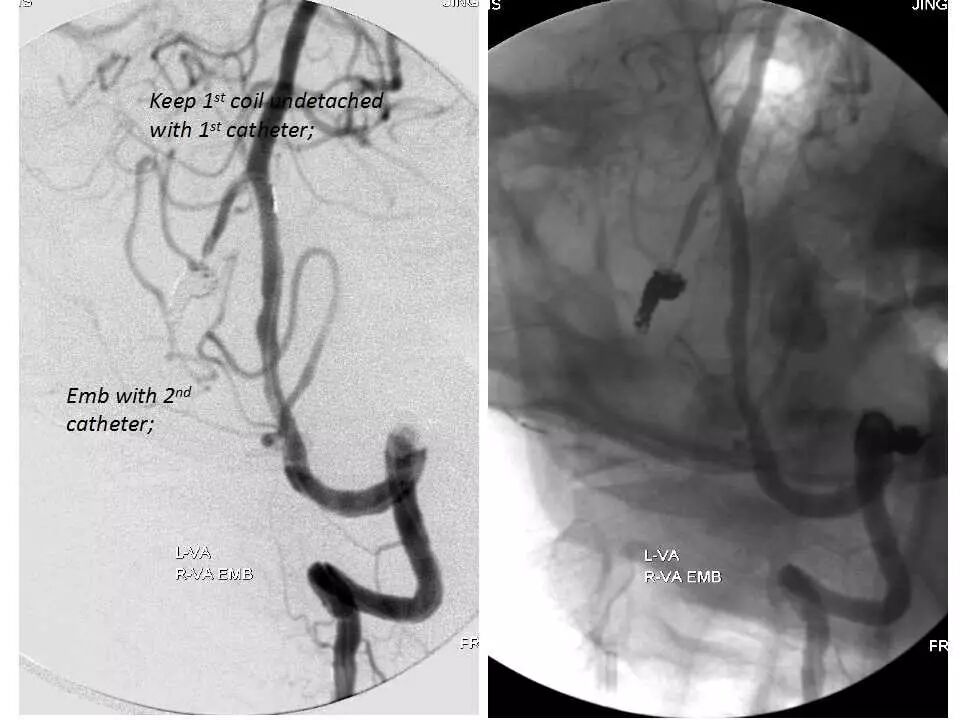

今天为大家分享的是“强生医疗CNV-神经介入专栏”第十五期,由首都医科大学宣武医院何川教授带来的“颅内动脉瘤介入治疗”精彩讲课视频及PPT,欢迎观看、阅读。文章仅代表作者个人观点,如有不同见解,欢迎同道斧正!

何川 ,首都医科大学宣武医院副主任医师,中国医师协会神经介入专业委员会常务委员,长期从事脑血管病和脊髓血管病的手术及介入治疗和相关研究工作。首都医科大学神经外科博士,师从于中国神经介入开创人凌锋教授;日本东北大学医院脑血管病治疗科博士后,师从于日本国脑血管病血管内治疗的开创者高桥教授。